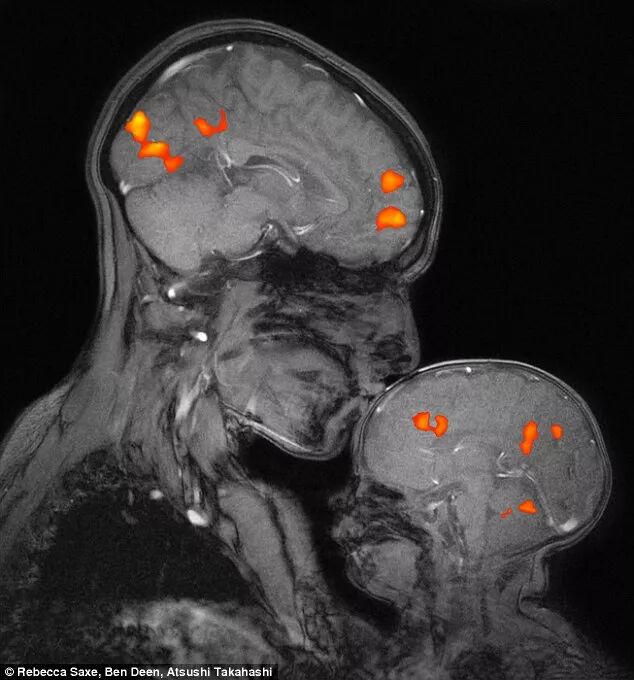

最能说明“两脑连动”的莫不如下面这个图像。这是普林斯顿大学神经学家Saxs和她2个月大的儿子Percy一同做的核磁共振。为了能证明母子大脑能共振,她用特制的核磁共振设备拍摄多次,才获得了这个理想的照片。注6

外行人看到的是两个形状相似,尺寸不同的大脑。

脑神经学家从这个图像能看到:半睡眠的婴儿,大脑中的血管随着母亲的吹眠歌声在轻轻的扩张!